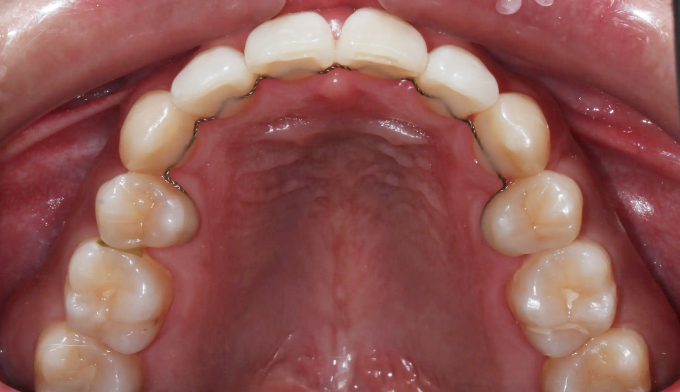

주걱턱과 돌출입, 그리고 덧니를 한꺼번에 가지고 있는 경우입니다. 이 모두를 해결하기 위해서는 필요한 공간의 양이 많기 때문에 성인에서는 작은어금니 발치가 대부분 필요합니다.

교정치료를 통해 치열이 고르게 된것은 물론, 주걱턱과 돌출입이 개선되면서 입술 모양이 보다 더 자연스러워지고 안모가 개선되었습니다.

총 교정치료는 21개월입니다.